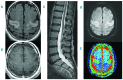

Bing Neel syndrome is a rare disease manifestation of Waldenström's macroglobulinemia that results from infiltration of the central nervous system by malignant lymphoplasmacytic cells. In this guideline we describe the clinical symptoms, as well as the appropriate laboratory and radiological studies, that can aid in the diagnosis. The presentation of Bing Neel syndrome may be very diverse, and includes headaches, cognitive deficits, paresis, and psychiatric symptoms. The syndrome can present in patients with known Waldenström's macroglobulinemia, even in the absence of systemic progression, but also in previously undiagnosed patients. Diagnostic work-up should include cerebral spinal fluid analysis with multiparameter flow cytometry to establish B-cell clonality, protein electrophoresis and immunofixation for the detection and classification of a monoclonal protein as well as molecular diagnostic testing for immunoglobulin gene rearrangement and mutated MYD88. MRI of the brain and spinal cord is also essential. The second challenge is to expand our knowledge of prognosis and treatment outcome. Prospective clinical trials on Bing Neel syndrome patients that employ uniform treatment along with appropriate laboratory cerebral spinal fluid assessments and standardized MRI protocols will be invaluable, constituting a significant step forward in delineating treatment outcome for this intriguing disease manifestation.